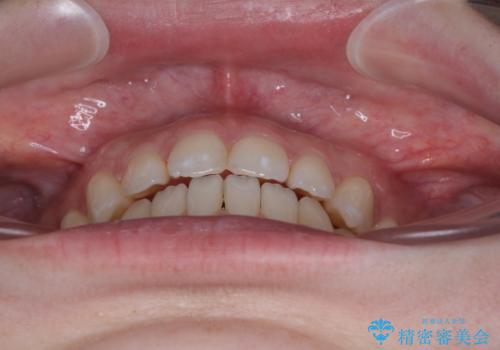

すきっ歯をインビザラインできれいな歯並びに改善

- 前歯の隙間を気にして来院された患者様です。

隙間や叢生の程度はそれほど著しいものではなかったので、インビザラインでもワイヤー矯正でも対応可能でしたが、極力目立たない装置を希望されたため、インビザラインにて矯正治療を行うこととしました。

すきっ歯の原因は色々ありますが、嚥下や発音時の舌突出癖が大きな原因となることがあります。

こちらの患者様も強い突出癖があったため、舌のトレーニング指導を行いました。